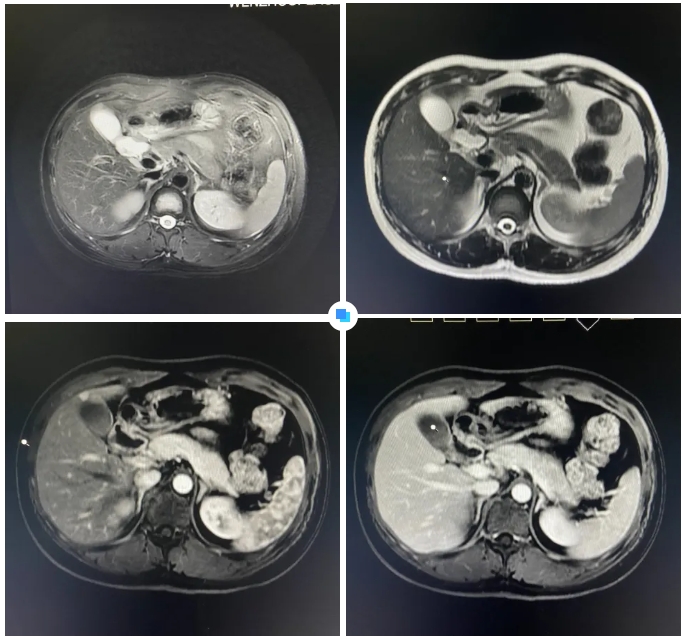

在被問(wèn)到如何發(fā)現(xiàn)隱藏如此深的病灶時(shí),和平國(guó)際醫(yī)院影像中心執(zhí)行主任侯文杰講到,該病灶在平掃T1、T2項(xiàng)都非常不清楚,只有彌散加權(quán)的情況下,病灶區(qū)域顯示出輕微的高信號(hào),這一細(xì)微線索引起了他的高度關(guān)注。

隨后的增強(qiáng)核磁掃描發(fā)現(xiàn),在動(dòng)脈期病灶顯著強(qiáng)化,而在門(mén)脈期明顯減退,這一特征與微小肝癌的表現(xiàn)高度吻合。